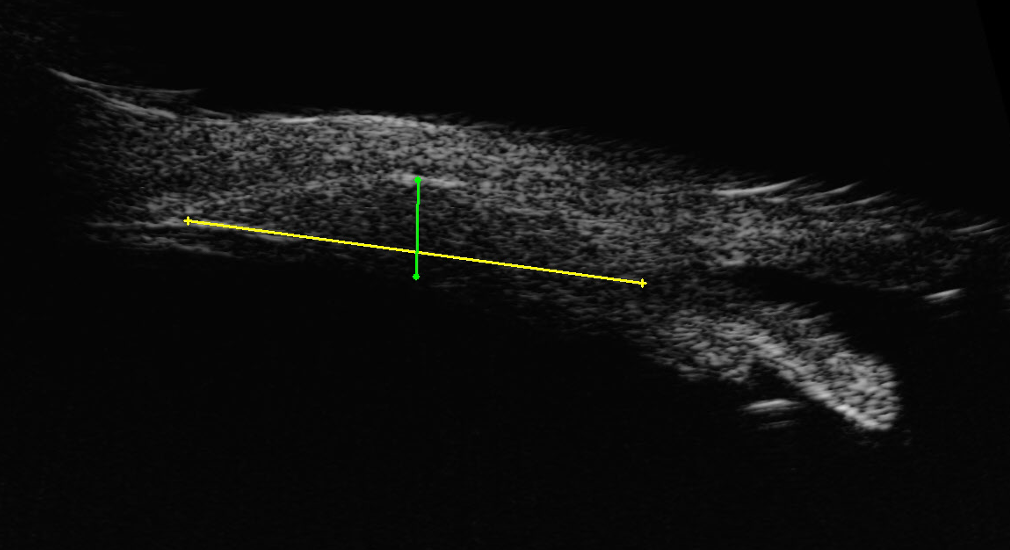

The spotted area of concern was so anterior in the eye that the corresponding internal area could not be easily examined with routine dilation, and a specialized ultrasound was performed to evaluate the internal structure of the wall of the eye. This “anterior b-scan” detected an abnormality. Underneath the pigmented spots of the sclera a tissue mass was found in the ciliary body, which is a ring like anterior structure which is located behind the iris and limbus. She was diagnosed with a melanoma of the ciliary body which was connected to the pigmented spots of the surface.

Treatment of ocular melanoma depends on the size and location of the tumor. Large melanomas are treated with enucleation of the eye, yet her tumor was not considered to be large by conventional methods. With the careful ultrasound exam, the tumor size was determined to be 1.2 mm thick with a largest diameter of 9.0 mm and a cross diameter of 5.7 mm. This made it a small melanoma per standard classification. Although such a small tumor could be observed carefully for signs of growth, the concern was that it had already demonstrated an invasive nature, and treatment with radiation was recommended. Consultation with a radiation oncologist was made, and a plan to perform episcleral plaque brachytherapy was created.